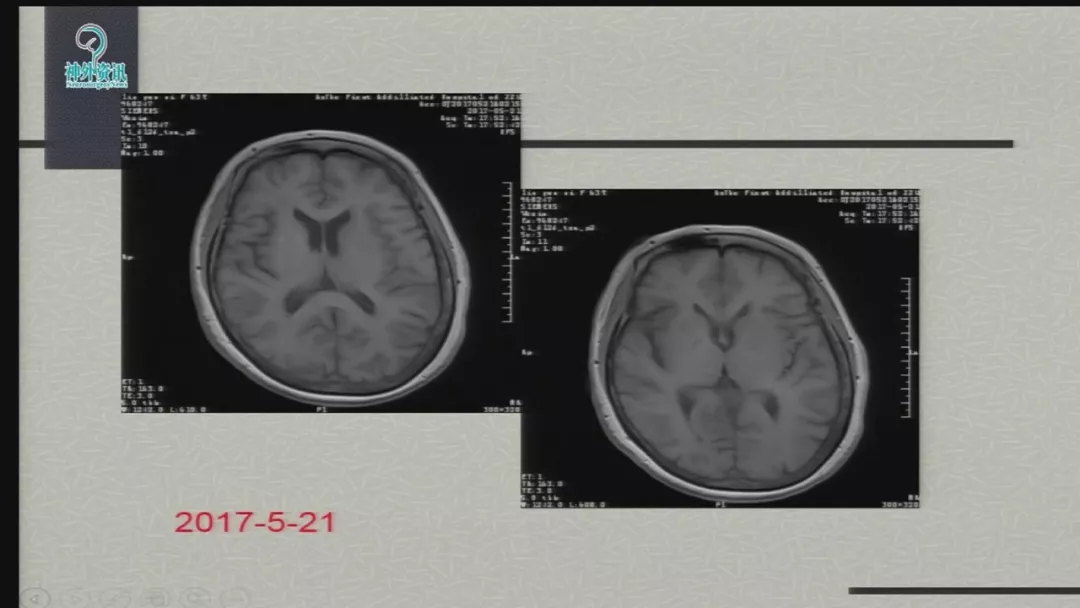

今天为大家分享的是由郑大一附院徐浩文教授在第七届全国介入医学工程大会上带来的“Neuroform EZ在ICAD治疗中的应用”精彩讲课视频和PPT,欢迎观看!(内容未经讲者审核,不当之处请与我们联系)